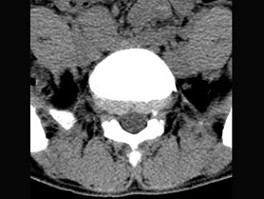

男,29岁,腰痛伴下肢轻度麻木,有外伤史,请结合所提供图像,选择最佳答案()

A.L 向前滑脱

向前滑脱

B.L 向后滑脱

向后滑脱

C.S 向前滑脱

向前滑脱

D.S 向后滑脱

向后滑脱

E.未见异常